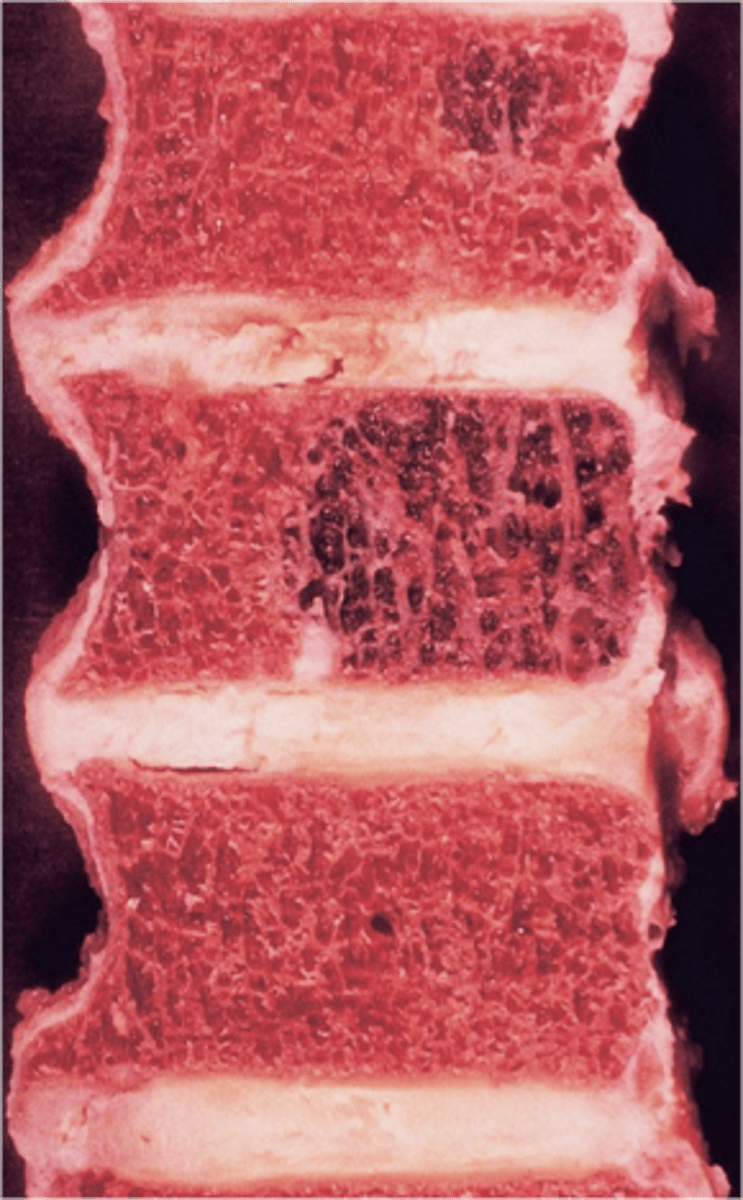

Vertebral hemangioma

- Solitary vascular neoplasm

- Slow growing

- 2-3% of all spine tumors (radiographs)

- 11% of all spines (autopsy)

- Most common benign tumor of the spine

State the incidence of vertebral hemangioma

- First seen over 40 y.o.

- F>M

- Most asymptomatic

- 75% in spine and skull

- Lower thoracic and upper lumbar

- Vertebral body

• Extension into vertebral arch (10-15%)

State the clinical features of vertebral hemangioma

- Vertical striations (corduroy cloth)

- Expansion (rare) may result in neurologic findings

- Skull ("sand dollar")

- Paravertebral swelling

State the radiographic features of vertebral hemangioma

Expansile

_____ vertebral hemangioma

- Left: Paget Disease

- Middle: Vertebral hemangioma

- Right: Osteoporosis

Complete the DDx for vertebral hemangioma